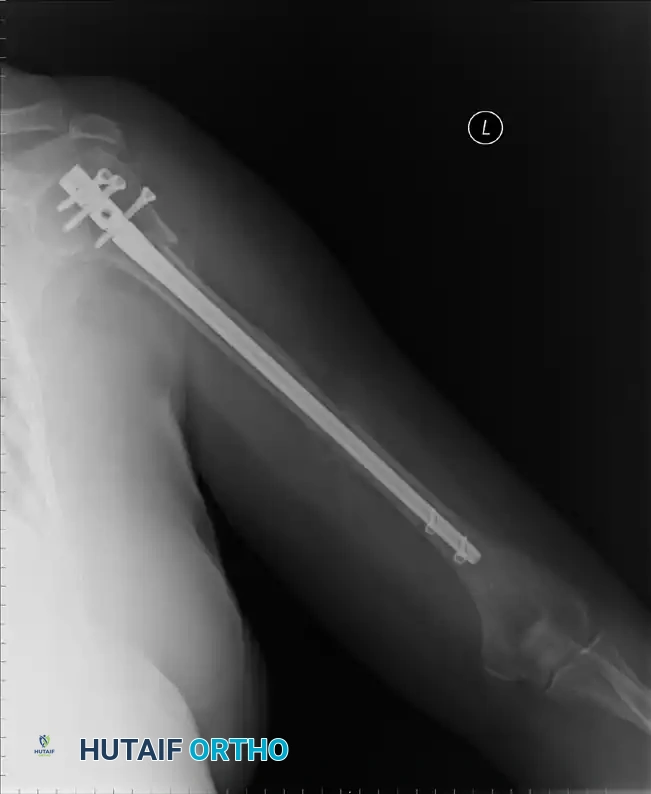

التثبيت باستخدام المسمار النخاعي

يوفر المسمار النخاعي ثباتاً ميكانيكياً قوياً جداً، حيث يتم إدخاله داخل التجويف النخاعي لعظمة العضد. يُعتبر هذا الخيار مثالياً للكسور التي تمتد إلى منتصف ذراع المريض.

من أهم مميزات المسمار النخاعي أنه يوفر تثبيتاً ممتازاً حتى في العظام الضعيفة، ولا يحتاج لشق جراحي كبير. التصميمات الحديثة لهذه المسامير تحتوي على براغي قفل متعددة الزوايا تمنع العظام من الانزلاق. ومع ذلك، يتطلب إدخال المسمار شق جزء صغير من وتر العضلة فوق الشوكية، مما قد يسبب بعض الألم المؤقت في الكتف بعد العملية.

إليك بعض الصور الإشعاعية والرسوم التوضيحية الإضافية التي توضح أشكال التثبيت الجراحي المختلفة لكسور أعلى عظمة العضد